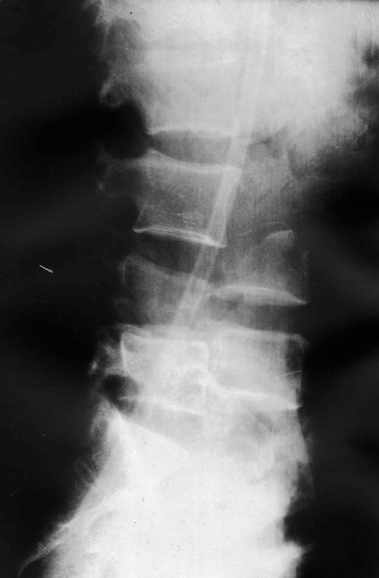

Поступил мужчина 37 лет. Автотравма - перевернулся на машине.

При поступлении состояние тяжёлое. Диагноз: "Оскольчатый перелом тела L3 позвонка, переломы корней дуг L3, l4 позвонков, дислокация (птоз) тел l3, L4 позвонков, множественные флотирующие переломы рёбер слева, гемопневматоракс". При всём при этом практически никакой неврологической симптоматики (легкое онемение по наружной поверхности левого бедра) функции тазовых органов не нарушены, движения в нижних конечностях сохранены. КТ сделать нет технической возможности, сканы рентгенограмм плохого качества поэтому высылаю скиаграммы. Рентгенограммы пришлю позже. Встало два вопроса: Теоретический - как грамотно сформулировать диагноз позвоночной травмы? Практический - тактика оперативного лечения позвоночной травмы. В настоящий момент сосстояние пациента стабилизировалось. С уважением Андрей Стасюк

Высылаю рентгенограммы. Спасибо за рекомендации. Наша тактика согласуется с вашими рекомендациями за исключением транспедикулярной фиксации - у данного пациента на наш взгляд предпочтительнее наружная транспедикулярная фиксация (Курганский аппарат). Погружная конструкция предпологает одномоментную репозицию до выполнения забрюшинного доступа и ревизии переломов что теоретически может привести к повреждению дурального мешка и корешков. АВФ позволит восстановить ось позвоночника и смещение по длине непосредственно под контролем глаза на этапе внебрюшинного доступа. Сколько сегментов замыкать? Я думаю может потребоваться замкнуть и сегмент L2-L3. Предполагается использовать тело L4 для костной пластики таким образом, чтобы ширина спиномозгового канала на уровне оперированных сегментов была увеличена. Фиксация тел позвонков вентральной пластиной.